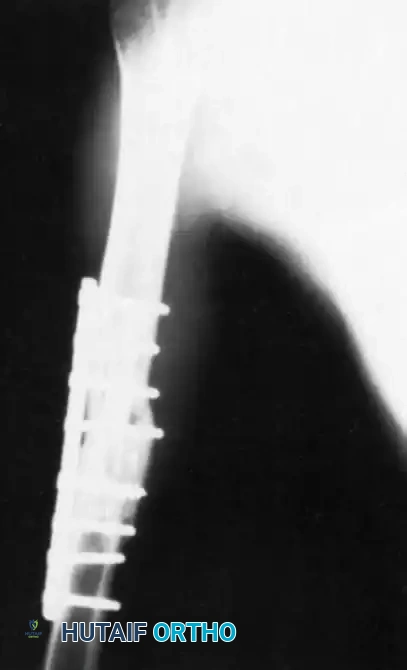

Image

FIGURE 59-9: Anteroposterior radiograph of the humerus 5 months after insertion of a fibular allograft and compression plating with a 4.5-mm dynamic compression plate, revealing evidence of bridging callus formation and incorporation of the allograft. (From Crosby LA, Norris BL, Dao KD, et al: Humeral shaft nonunions treated with fibular allograft and compression plating, Am J Orthop 29:45, 2000.)